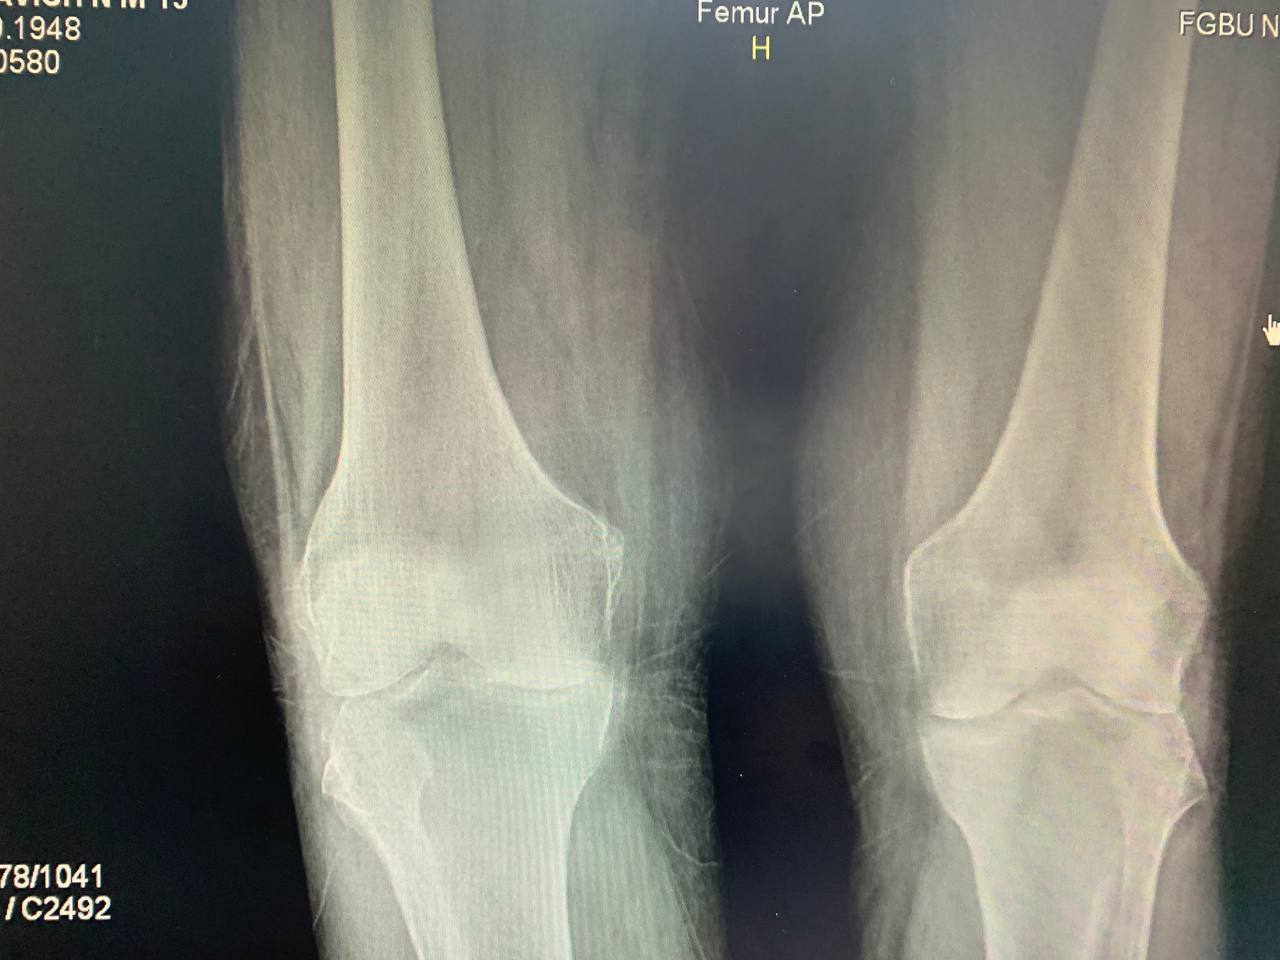

Коллеги, какую бы стадию гонартроза вы бы поставили справа?

3-4 ст

Я бы склонился чисто к 3-й, но много зависит от клиники.

З-я по Косинской